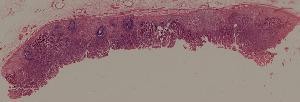

59.慢性萎缩性胃炎

低倍视野